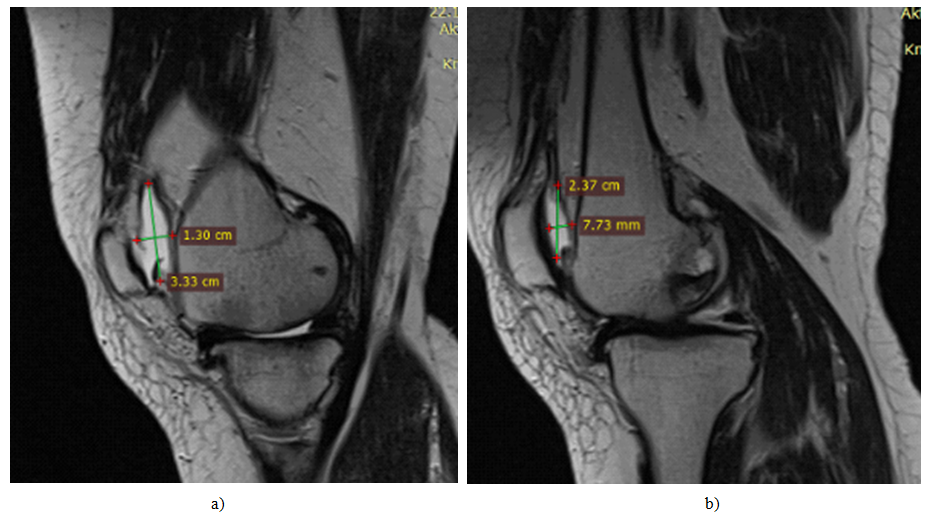

Figure 2. MRI picture of synovial fluid volume. a)-before surgical intervention. b)-after 6 months of surgical intervention.

Figure 3. MRI picture of cartilage defect, osteophyte volume. a)-before surgical intervention. b)-after 6 months of surgical intervention